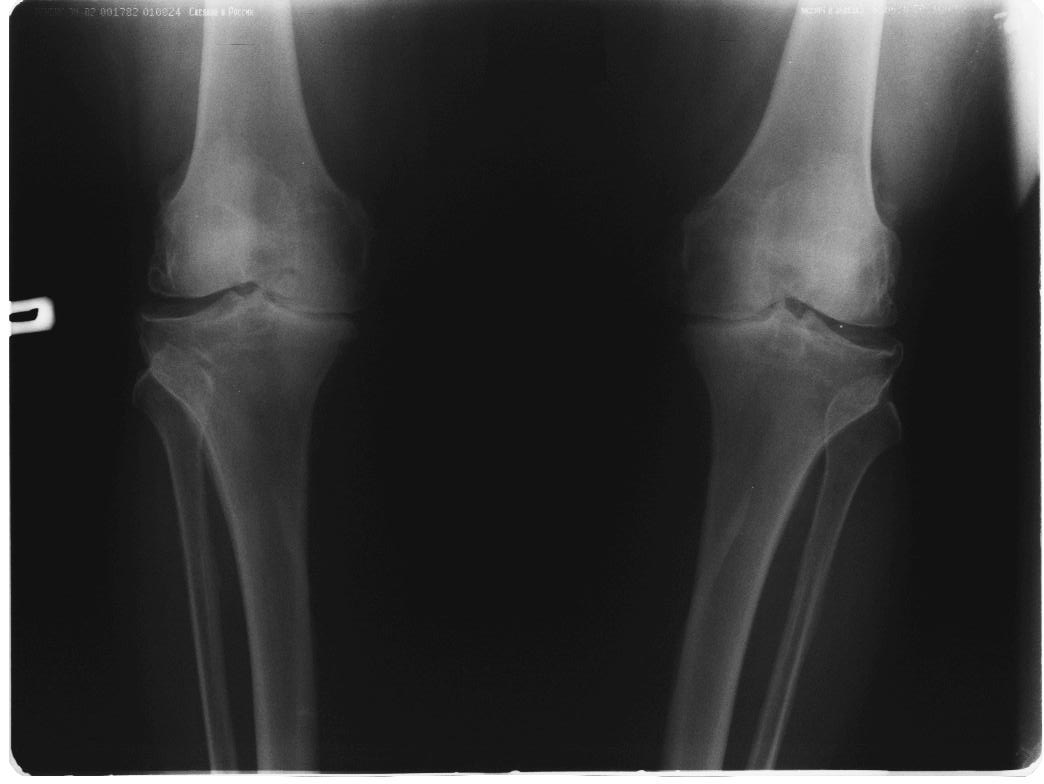

вообще, то в комплекс симптопатической терапии входят всякие медикаменты + ИСЖ (гиалуронаты) + гормоны при "мокром" суставе + физиолечение + грязи + солнце - воздух и вода + доброе слово и участие доктора и все это.... не удел ортопеда -хирурга. Это ближе к терапии. Чуть агрессивнее различные артроскопические санации и манипуляции - временно помогает + ИСЖ + фиксаторы + ортезы + аппараты + трость и костыли + коляска. Однако судя по рентгенограммам - суставы приговорены к эндопротезированию.

Откровенно говоря, прочитав ваше суждение по теме о возможности неоперативного лечения двустороннего гонартроза, варусной деформации,сильно

Каждому методу свое время и место. у обсуждаемого пациента очевидна перегрузка медиальных отделов суставов с разрушенными суставными поверхностями, каким образом, вы представляете себе облегчить боли НПВП (разнообразие которых столь велико, что больному не хватит жизни и здоровья, чтобы все перепробовать, но идля *участливого* доктора всегда есть путь к отступлению - не помогает один, давайте попробуем другой - бесконечный,

Я всячески поддерживаю тактику оперативного вмешательства. Но просто тема консервативного лечения, надеюсь Вы согласитесь, на форуме обсуждается КРАЙНЕ РЕДКО И НЕОХОТНО. А применительно к выложенным R-граммам, конечно, показано Эндопротезирование, но только заголовок обращения сразу расставляет приоритеты в пользу консервативных методик. Причины тому могут быть самые разнообразные, нам о них не сообщили. Так зачем же предлагать коллегам то, чего они делать не будут?